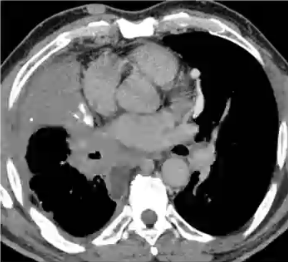

❖ 急性和亚急性期:单/双肺结节,伴/不伴双肺弥漫斑片影,常伴有纵隔和肺门淋巴结增大

❖ 纤维性纵隔炎是其晚期较为少见但严重的并发症